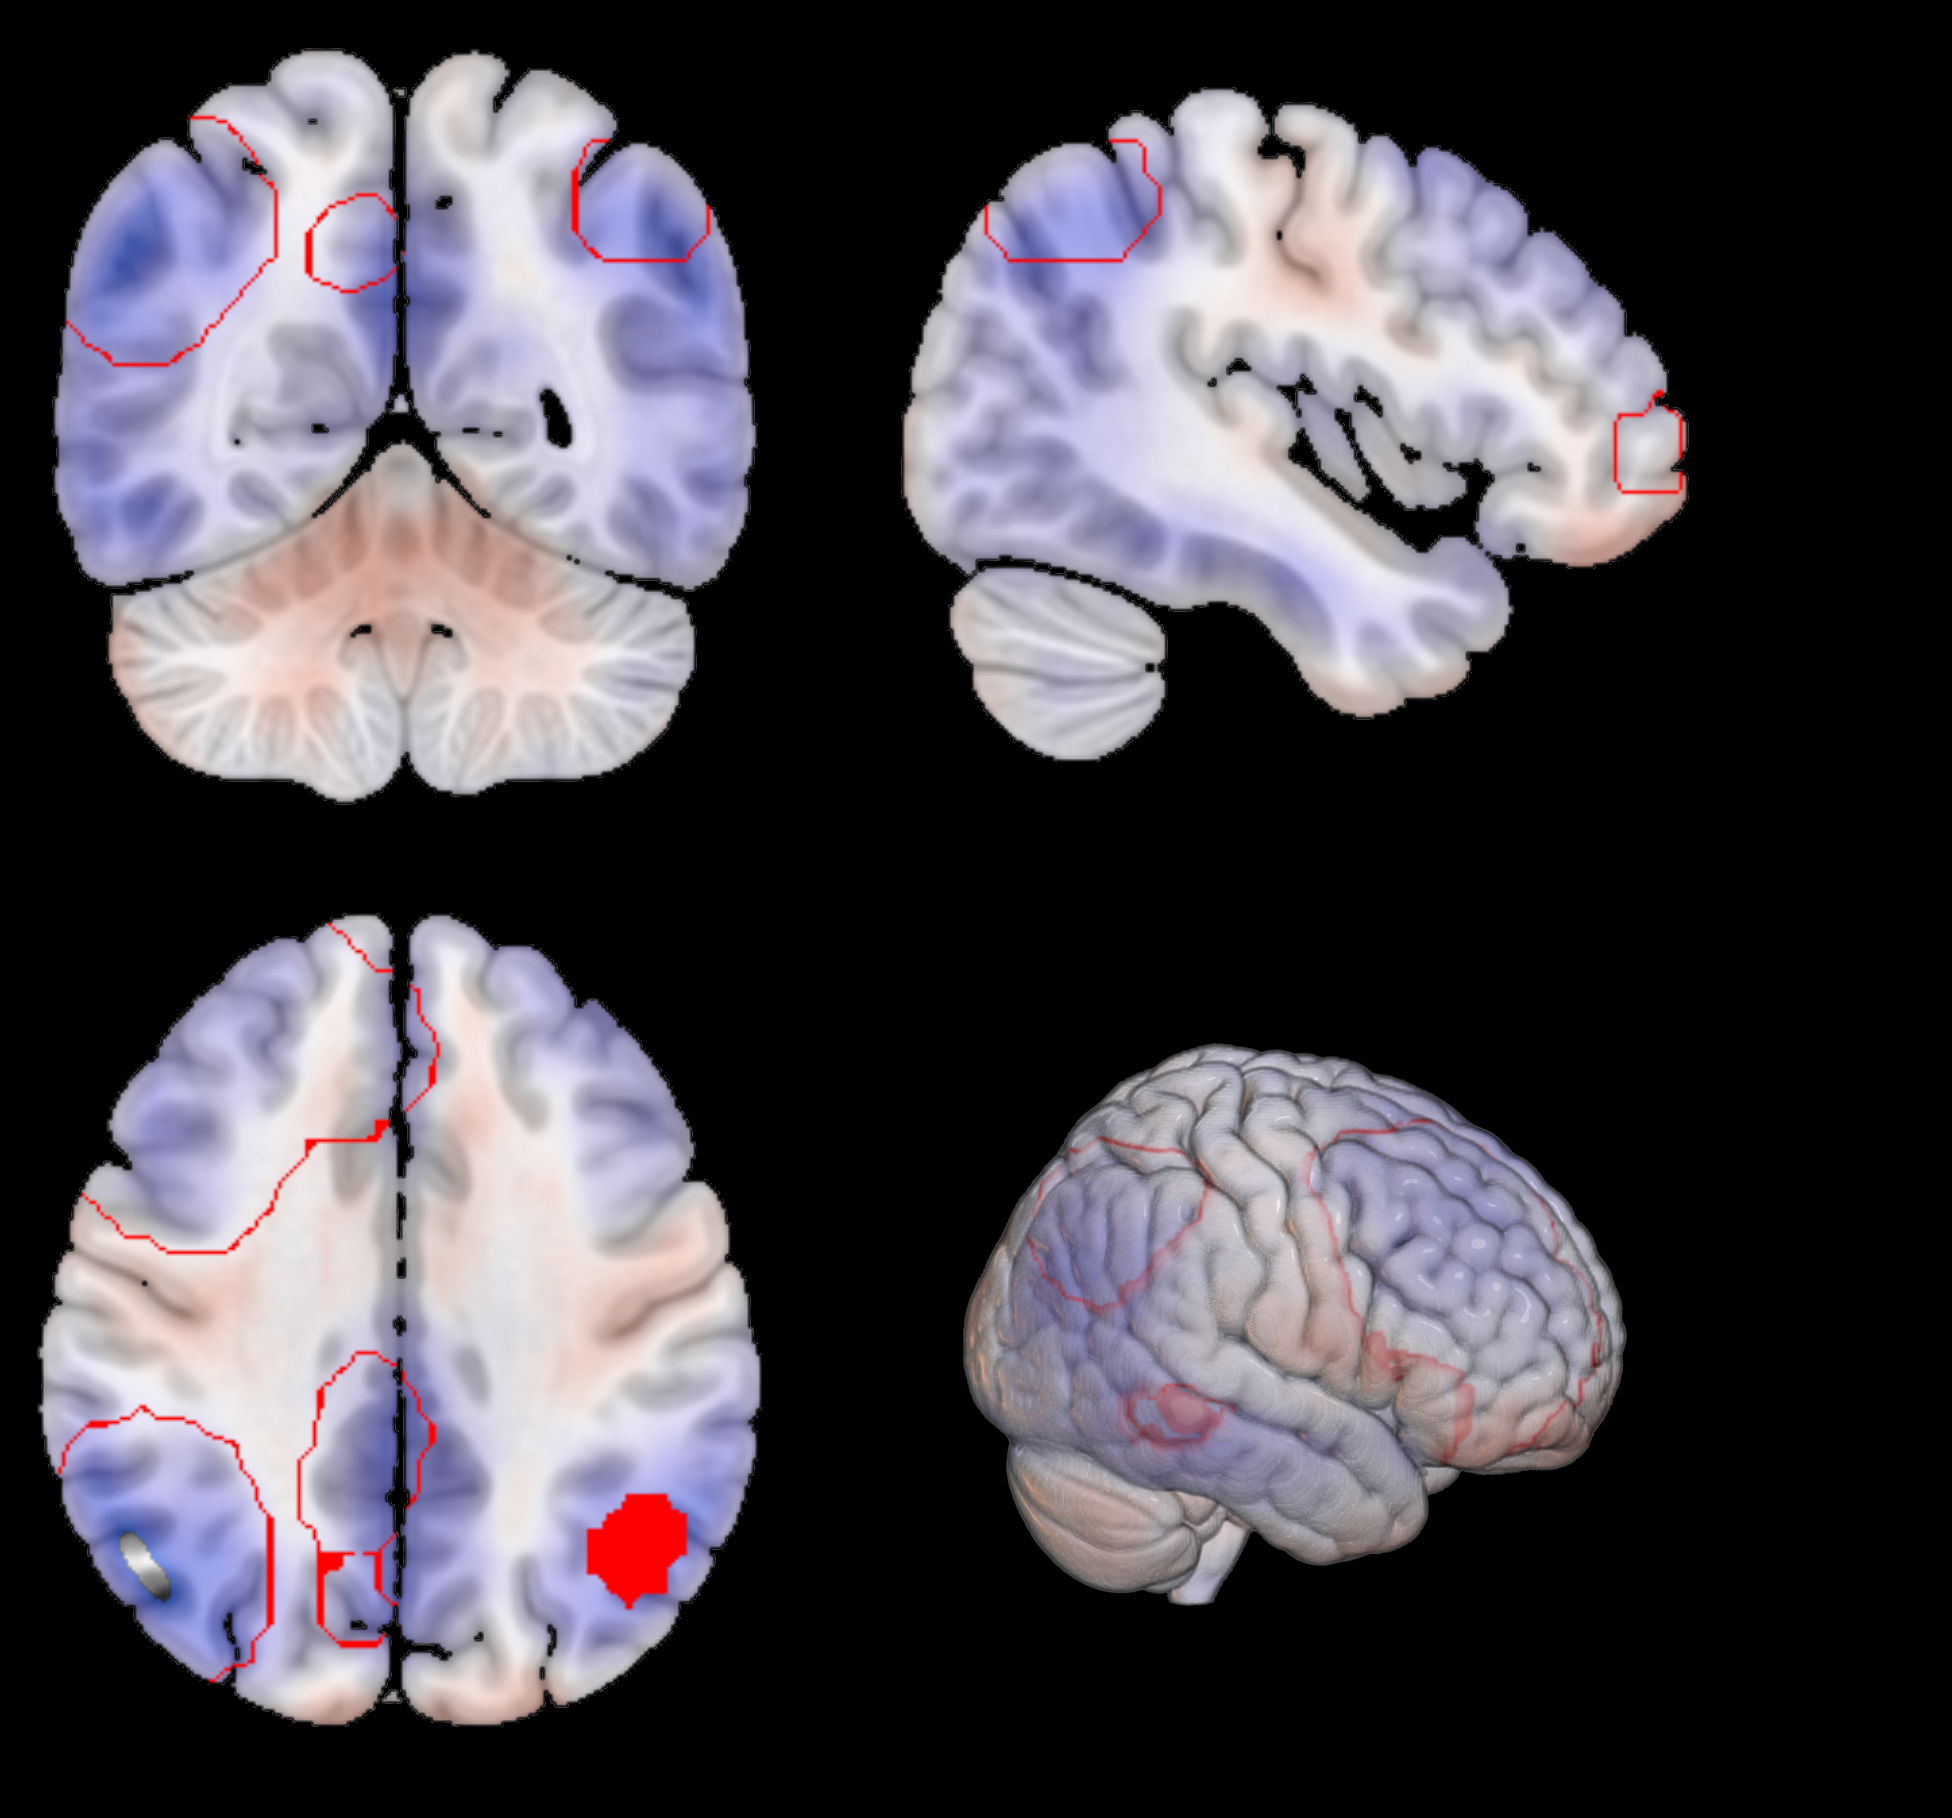

To further investigate the biological relevance of , we generated average latent representations corresponding to fixed values of this variable within its observed range (see Fig. 5). These representations were decoded into brain space, and a voxel-wise GLM was applied to identify structural changes. The resulting statistical map (Fig. 7) highlights regions most affected by neurodegeneration. Decreased metabolism (in blue) was predominantly observed in the prefrontal and medial temporal cortices, as well as in parts of the occipital lobe. In particular, Fig. 7(d) reveals a well-defined decline in metabolic activity in the hippocampal region. In contrast, increased metabolism (in red) was found in the motor cortex and various subcortical structures, as found in literature Mosconi (2005); Minoshima et al. (1997); Robert B. Daroff (2016).

Additional insights are provided in Figs. 7(b), 7(c), 7(e), and 7(f), which show the voxel-wise GLM coefficients overlaid on key RSN s. These include the DMN and the left and right Fronto-Parietal Networks (FPNs). Both the DMN and FPN s demonstrated significant reductions in metabolic activity, whereas the Sensorimotor Network exhibited either no significant changes or slight increases in metabolism.

The generative nature of the VAE allowed us to map these dementia patterns back to brain space, providing an interpretable framework for visualizing the patterns learned by the model to distinguish between AD subjects and normal controls. By performing a GLM on reconstructions of subjects with different values of the first latent variable, we were able to visualize the variations due to dementia in the brain space (Fig. 7). We found that the patterns learned by the model correspond to well-known regions affected by the disease. A marked reduction in glucose metabolism is observed within the DMN —a well-established hallmark of AD Greicius et al. (2004); Buckner et al. (2008), as seen in Fig. 7(b). Similarly, Figs. 7(c) and 7(e) show that the CEN, which encompasses both FPN s, also shows reduced metabolic activity, in line with previous literature. The DMN is involved in internally directed cognitive processes such as introspection and memory retrieval, while the CEN supports functions like attention, working memory, and cognitive control Raichle et al. (2001); Seeley et al. (2007). These domains are significantly impaired in AD Sorg et al. (2007); Zhou et al. (2010); Brier et al. (2014), making the observed metabolic patterns both biologically plausible and interpretable.

In contrast, the Sensorimotor Network —typically preserved in AD —shows either a slight increase or no significant change in metabolic activity. These patterns are clearly localized by our model mainly to the precentral and postcentral gyri, areas responsible for voluntary motor control and somatosensory processing Mosconi (2005); Sperling et al. (2010). We observe a similar behavior in the central occipital cortex, which is also known to be unaffected by AD Scahill et al. (2002).